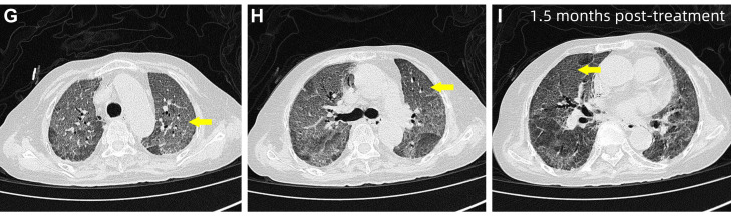

入院时行高分辨率CT(HRCT),显示双肺弥漫性斑片状致密影,边缘模糊,以双下肺为主,局部可见空气支气管征,提示急性弥漫性肺实质受累。

图1 患者入院时HRCT,双肺弥漫性斑片状致密影,边缘模糊,双肺下叶为主要受累区域,局部可见空气支气管征

住院第13天,患者病情短暂稳定后,在高流量氧疗(吸氧浓度65%,流量50L/min)支持下安全复查HRCT,显示双肺炎症明显加重,呈广泛磨玻璃影伴部分实变,肺间质受累加重,同时可见双侧胸腔积液及局灶性肺不张,较入院影像明显进展。

图2 患者住院第13天HRCT 图像,显示双肺弥漫性磨玻璃影伴部分实变(红色箭头),以双肺下叶为主,可见局部空气支气管征及双侧胸腔积液(右侧更为明显)